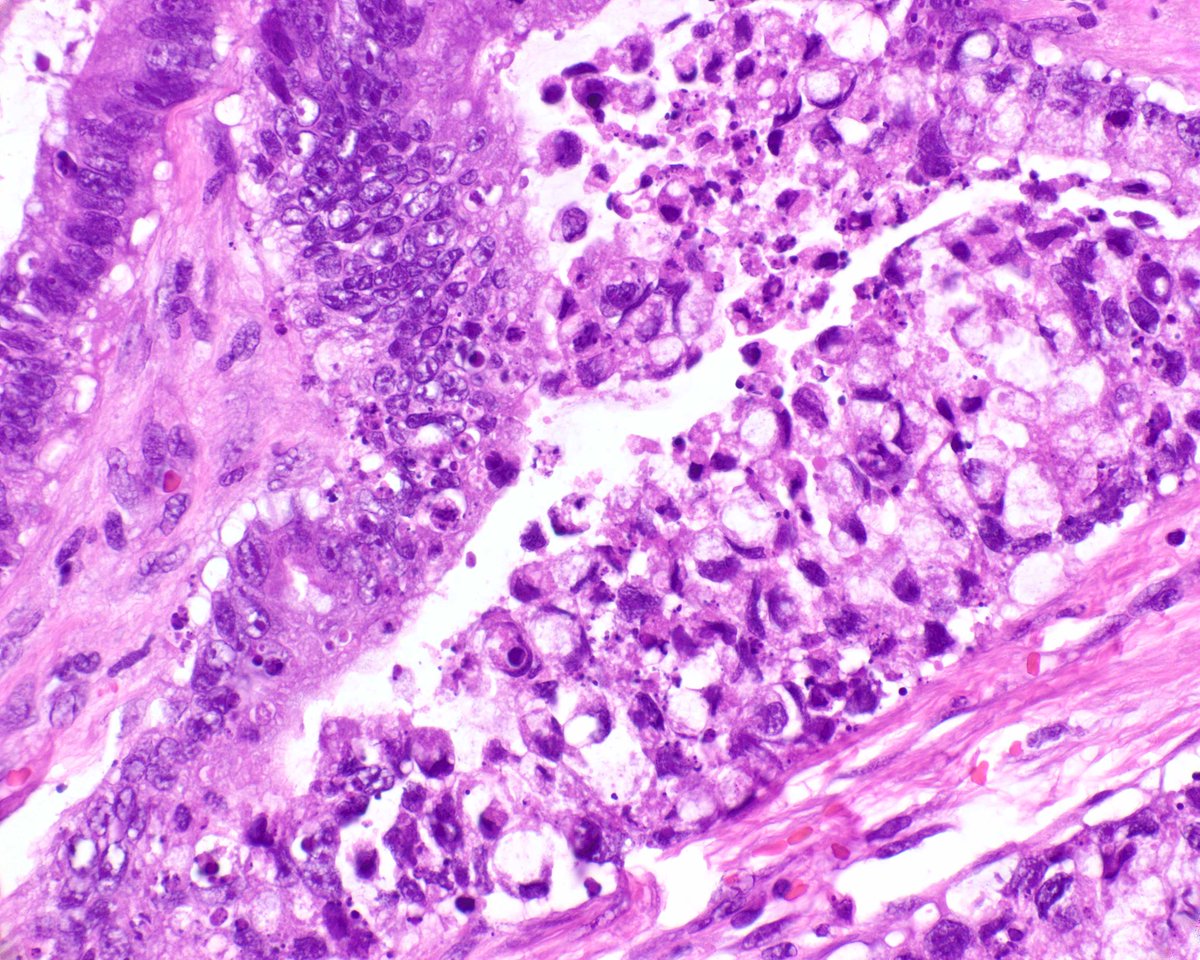

Placental Site Trophoblastic Tumor • RARE malignant trophoblastic neoplasm from intermediate trophoblasts • Mean Age: 31 • 2/3 cases follow full term pregnancy (median latency 12-18 months) • 🩺: Vaginal 🩸, uterine enlargement • ~25-30% may develop recurrent dz